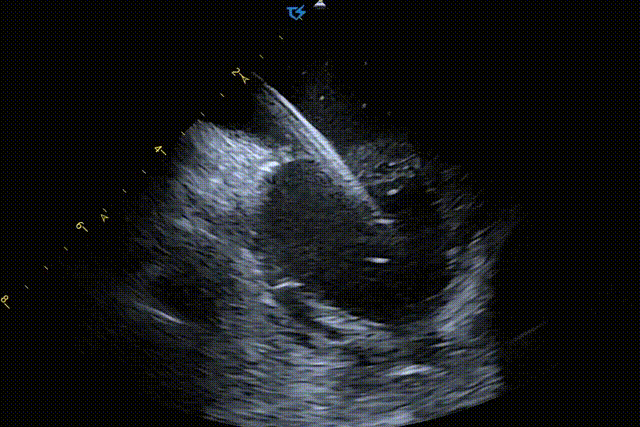

图2 ICE直视下室缺封堵全流程[1]